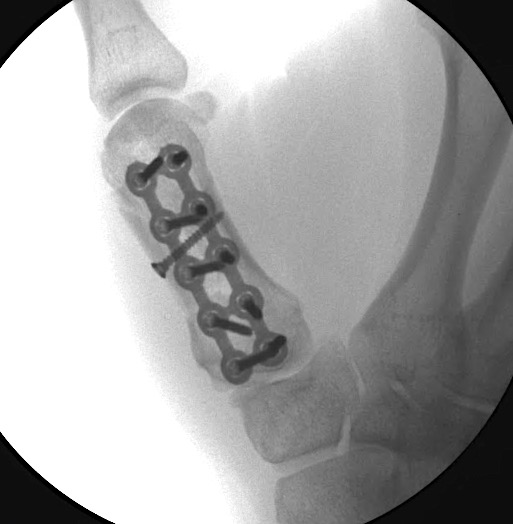

Case 1:

A 64-year-old male suffered a multi-fragmentary fracture of his right thumb metacarpal (Fig 1). An adapted 12-hole strut plate from the variable angle locking hand system was the implant of choice for fixation (Figs 2 - 4).

The strut plate provided good stability in a comminuted extraaricular fracture pattern and enables immediate mobilization. Bone callus formation was not witnessed during the healing process.